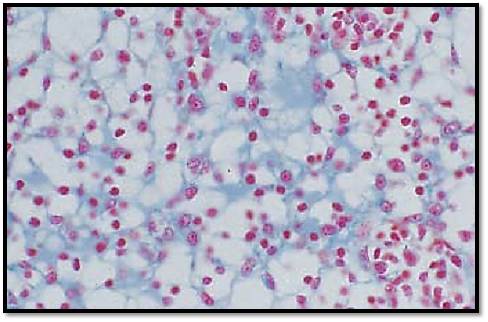

The lymphocytes in the outer layer of the cortex occur condense d in ovoid or round nodes, called follicles or noduli lymphatici . These follicles are the B-lymphocyte regions of the lymph node. The regions with T-lymphocytes are the diffusely delimited paracortical zones. Cortical nodes solely consist of densely packed small and me diumsized lymphocytes. They are called primary follicles. This preparation presents a secondary follicle. Apart from small lymphocytes, it contains in its center large cells with basophilic cytoplasm (centrocytes and centroblasts). These regions inside a follicle are called germinal centers 1 . They arise from primary follicles during immunogenesis. A lymphocyte barrier (corona) 2 surrounds the germinal center of a secondary follicle. It pre dominantly consists of small lymphocytes. Sporadically, plasma cells occur in the lymphocyte corona.

1 Germinal center

2 Lymphocyte corona (barrier)

Stain: azan; magnification: × 200